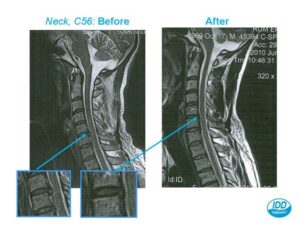

How MRI Supports IDD Therapy Treatment Planning

IDD Therapy (Intervertebral Differential Dynamics) is an advanced form of spinal decompression used to treat:

MRI plays a vital role in determining whether IDD Therapy is the right treatment.

Why MRI + IDD Therapy Works So Well Together

IDD Therapy gently distracts and decompresses the spine, reducing pressure inside the disc and allowing nutrients to flow in for healing. When combined with MRI findings, treatment becomes:

In many cases, patients who thought they might need injections or surgery instead make excellent progress with IDD Therapy after their MRI confirms suitability.